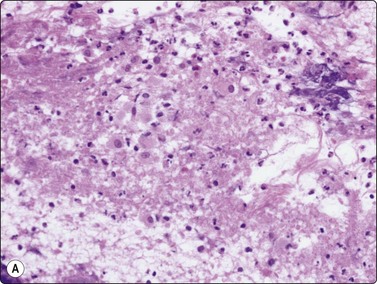

image image

Fig. 8.13 Anthraco-silicosis; progressive massive fibrosis

Bilateral upper zone/hilar lung masses in a miner. Dense masses of macrophages and fibrous tissue (A, H&E, MP; B, H&E, HP).